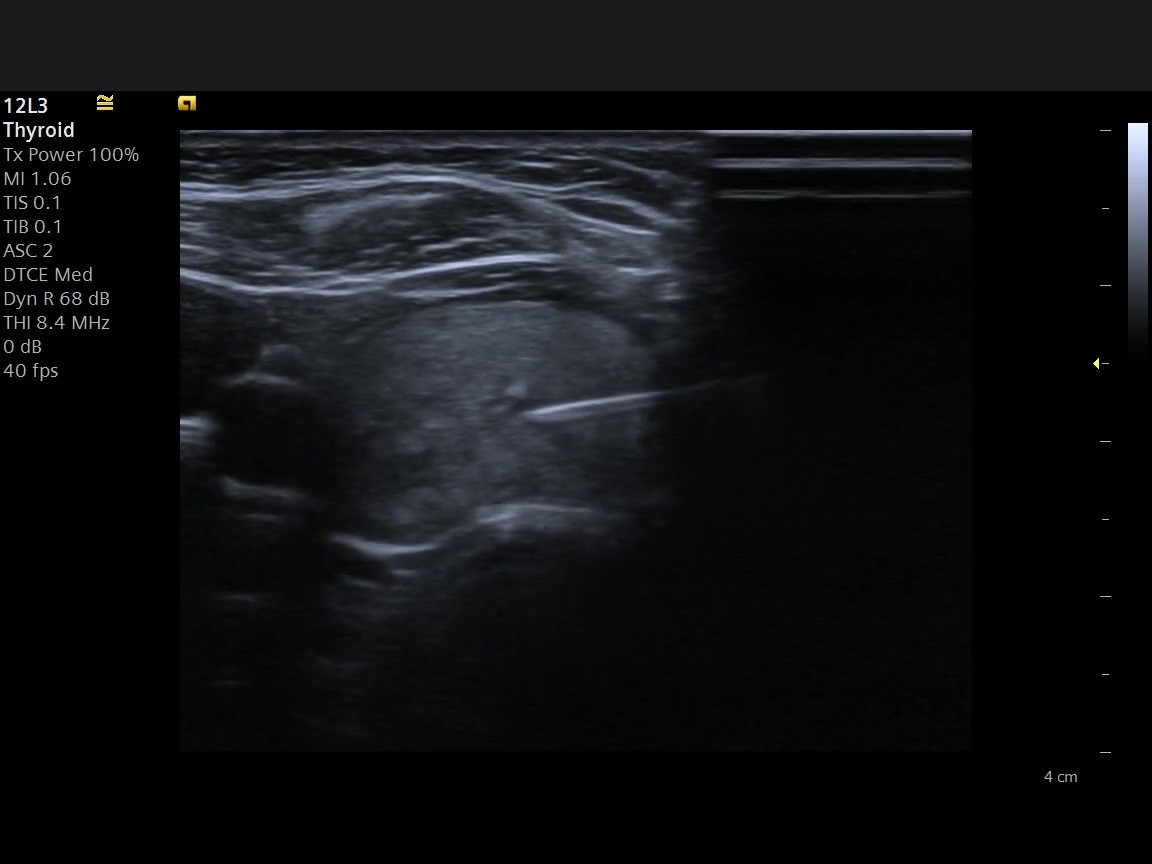

USG Eşliğinde Tiroid Biyopsisi Nedir?

Tiroid nodülü, toplumda oldukça sık görülen bir durumdur. Özellikle kadınlarda ve 40 yaş sonrası bireylerde tiroid bezinde nodül saptanma oranı artar. Mersin'de tiroid nodülü nedeniyle başvuran hastaların en sık sorduğu soru ise şudur: "Bu nodül tehlikeli mi?"